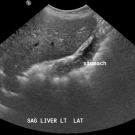

Sayed K. Ali, MD, FACP; Adam-Mahdi Jaffer; Hammad Bhatti, MD

A 58-year-old woman presented with a giant hepatic hemangioma, which had been detected via ultrasonography and abdominal computed tomography (CT) scans 6 years prior.